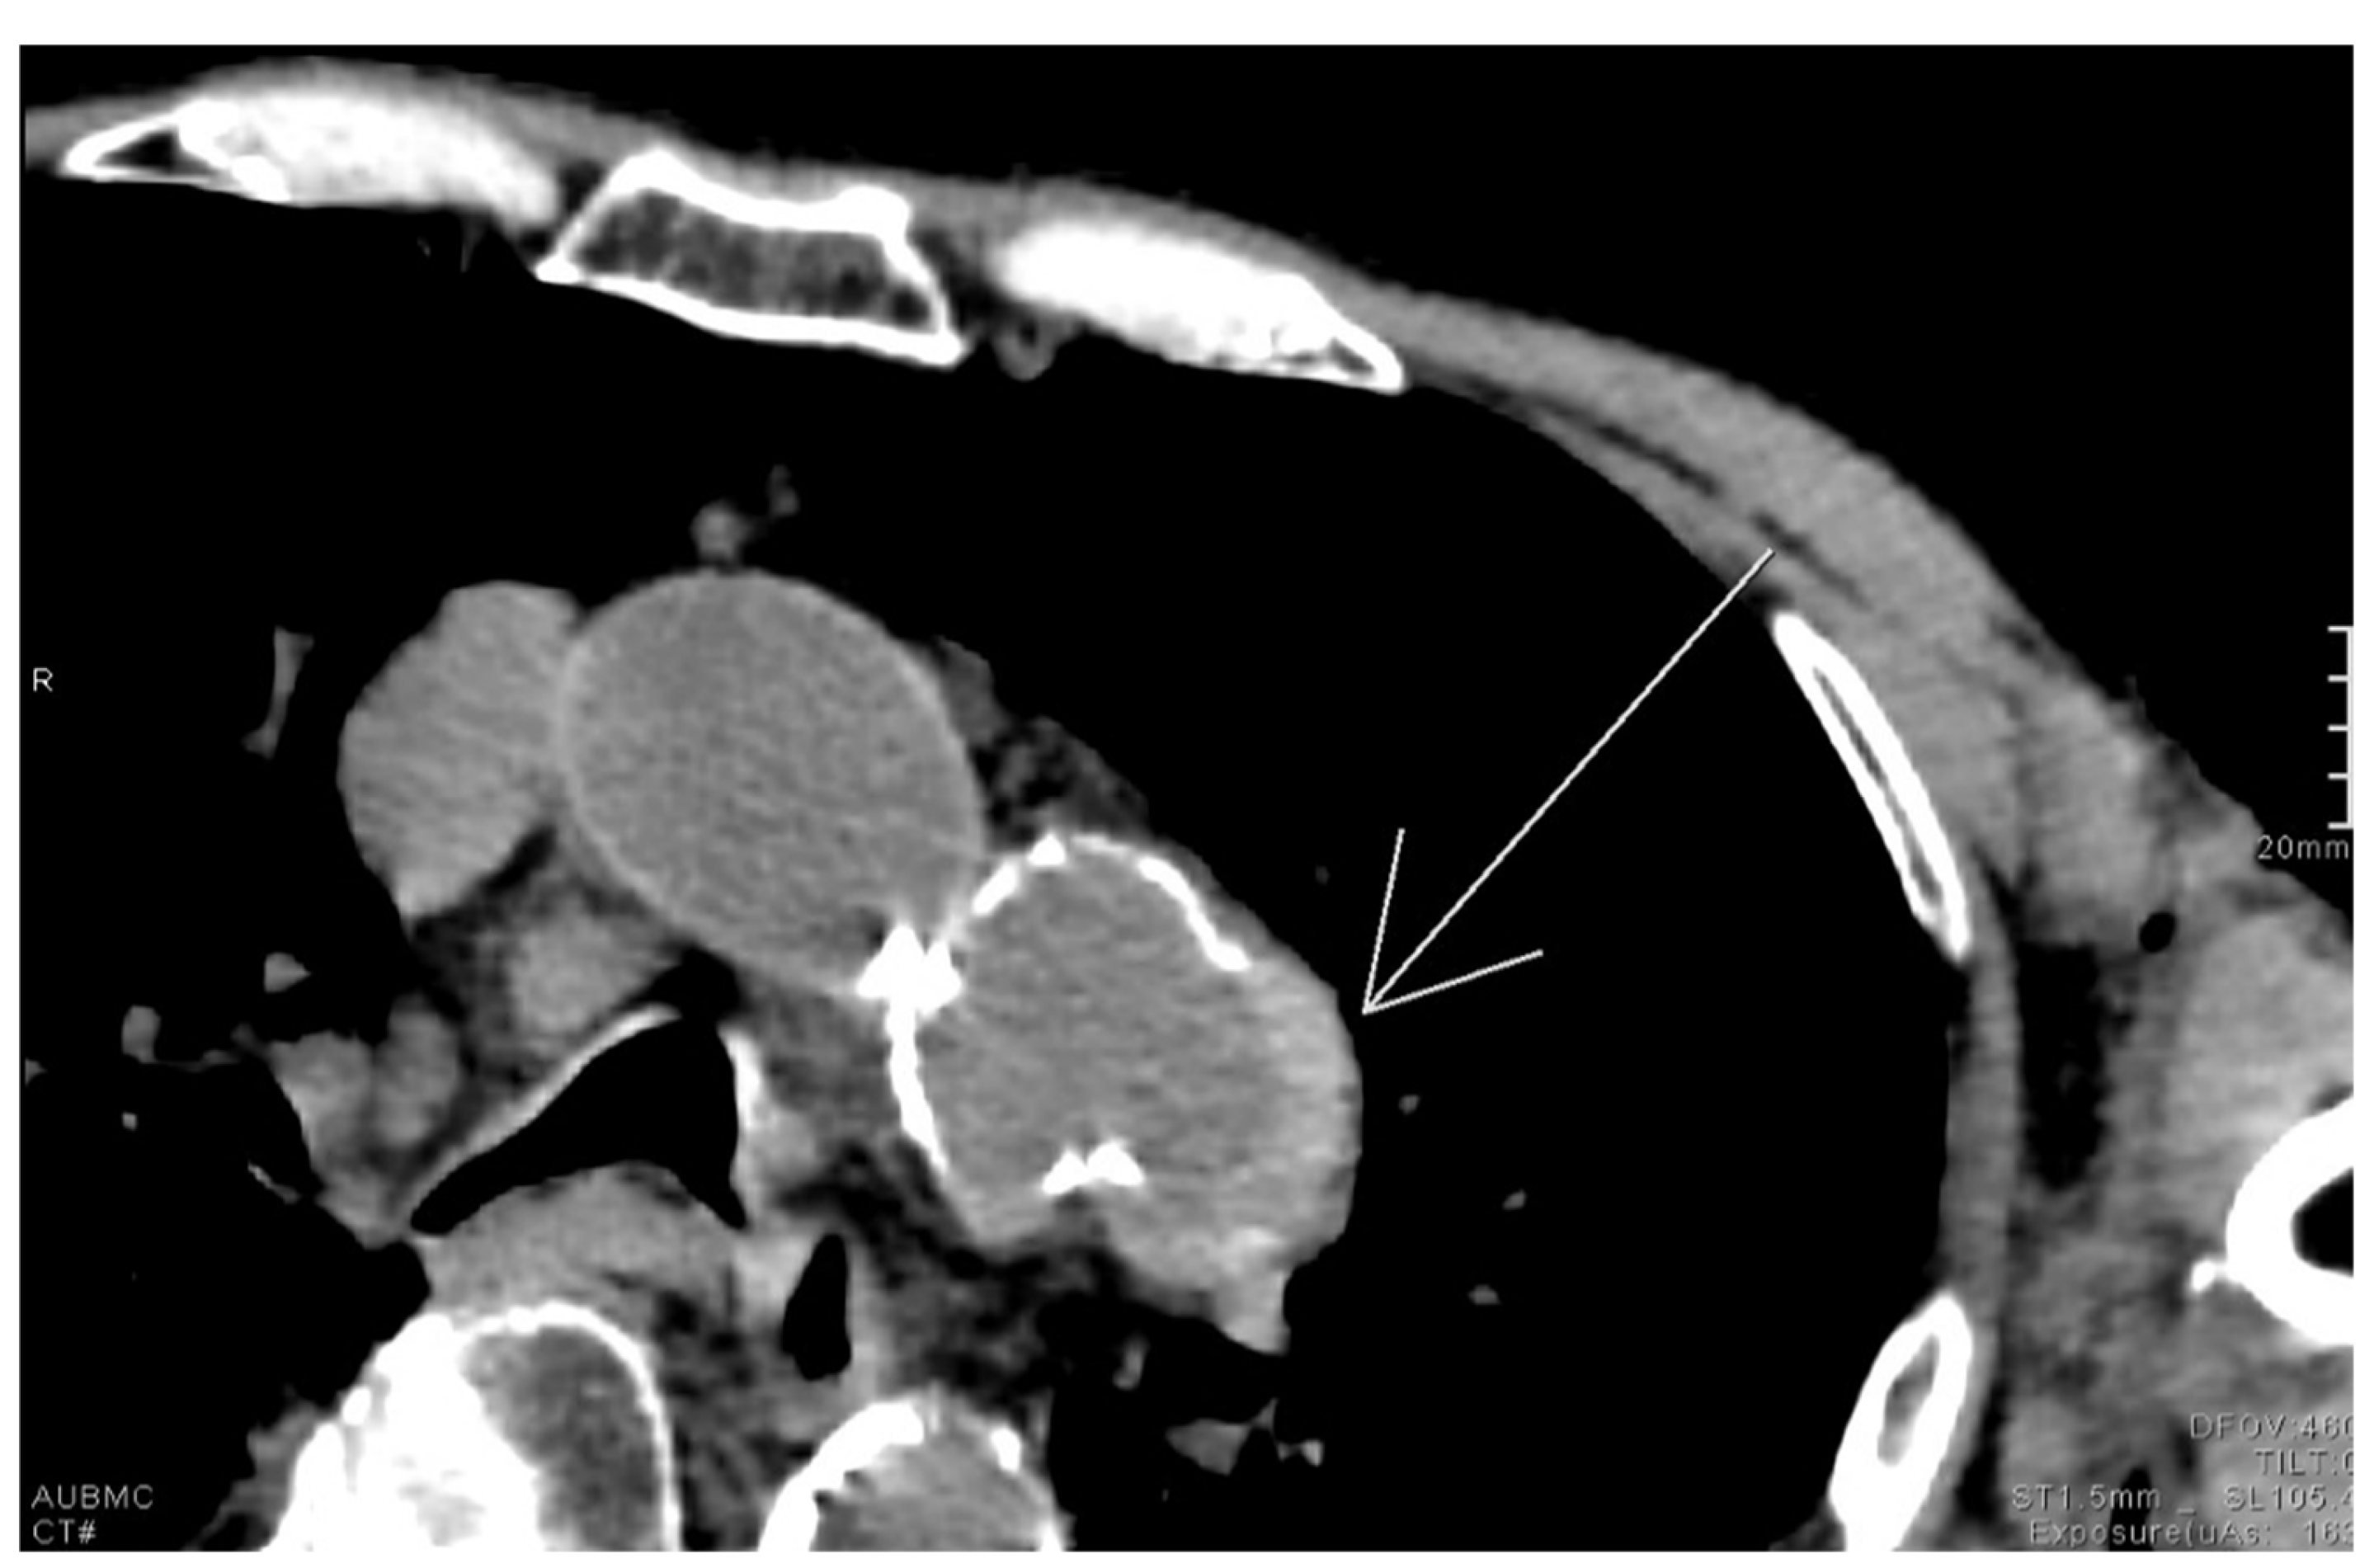

2.12. Hyperdense Cresent Sign

The hyperdense crescent sign, also known as the high-attenuation crescent sign, represents the accumulation of blood within an intraluminal thrombus or the wall of an aortic aneurysm. The sign is considered a warning of aneurysm instability and indicates a higher risk for imminent rupture. The sign is best seen on non-contrast CT scans of the chest or abdomen and develops due to the hyperattenuating nature of fresh blood compared to older thrombus or soft tissue (Figure 12). Patients with abdominal or back pain, hypotension, or a pulsatile abdominal mass who show a hyperattenuating crescent within the aortic aneurysm wall on non-contrast CT are at high risk of impending rupture. This finding signals wall instability and mandates urgent vascular surgery consultation and close hemodynamic monitoring [62].

Figure 12.

Unenhanced chest CT with findings of the hyperdense crescent sign noted along the left lateral wall of a saccular aneurysm arising from the distal aortic arch (white arrow).